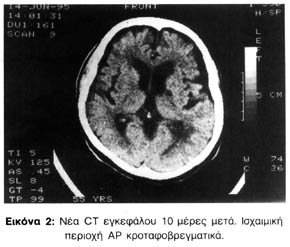

Η CT εγκεφάλου την ημέρα της εισαγωγής της (4-6-1995) έδειξε υπόπυκνη εστία παρά τα βασικά γάγγλια Α.Ρ με χαρακτήρες εμφράκτου, διάταση των κοιλιών και εγκεφαλική ατροφία, ιδιαίτερα στις πρόσΘιες περιοχές εγκεφάλου (εικόνα 1).